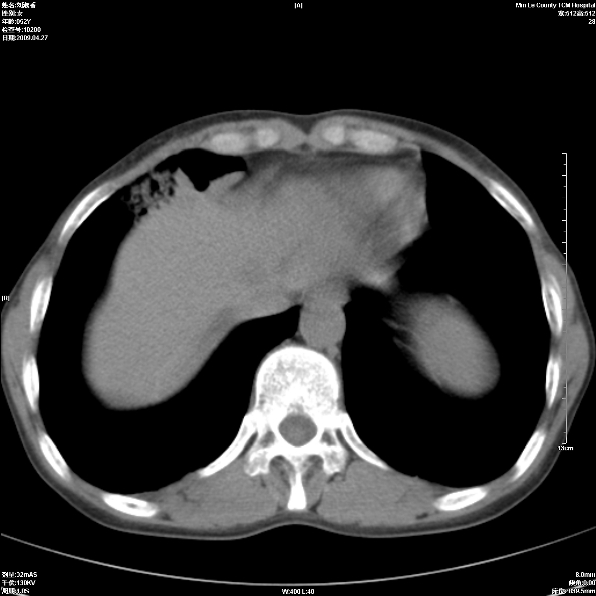

标题: CT19625:女52间断性喀血 [打印本页]

标题: CT19625:女52间断性喀血

考虑右肺中叶感染性病变并右肺中、下叶肺泡积血;建议抗炎、止血治疗后复查。

右肺中叶炎症;右肺中、下叶肺泡积血

右肺中叶支气管扩张并感染或咳血沉积,块右肺中下叶肺泡积血。

右肺中叶慢性炎症伴局部支扩并中下叶肺泡积血。

考虑右肺中叶感染性病变并右肺中、下叶肺泡积血。建议治疗后复查。